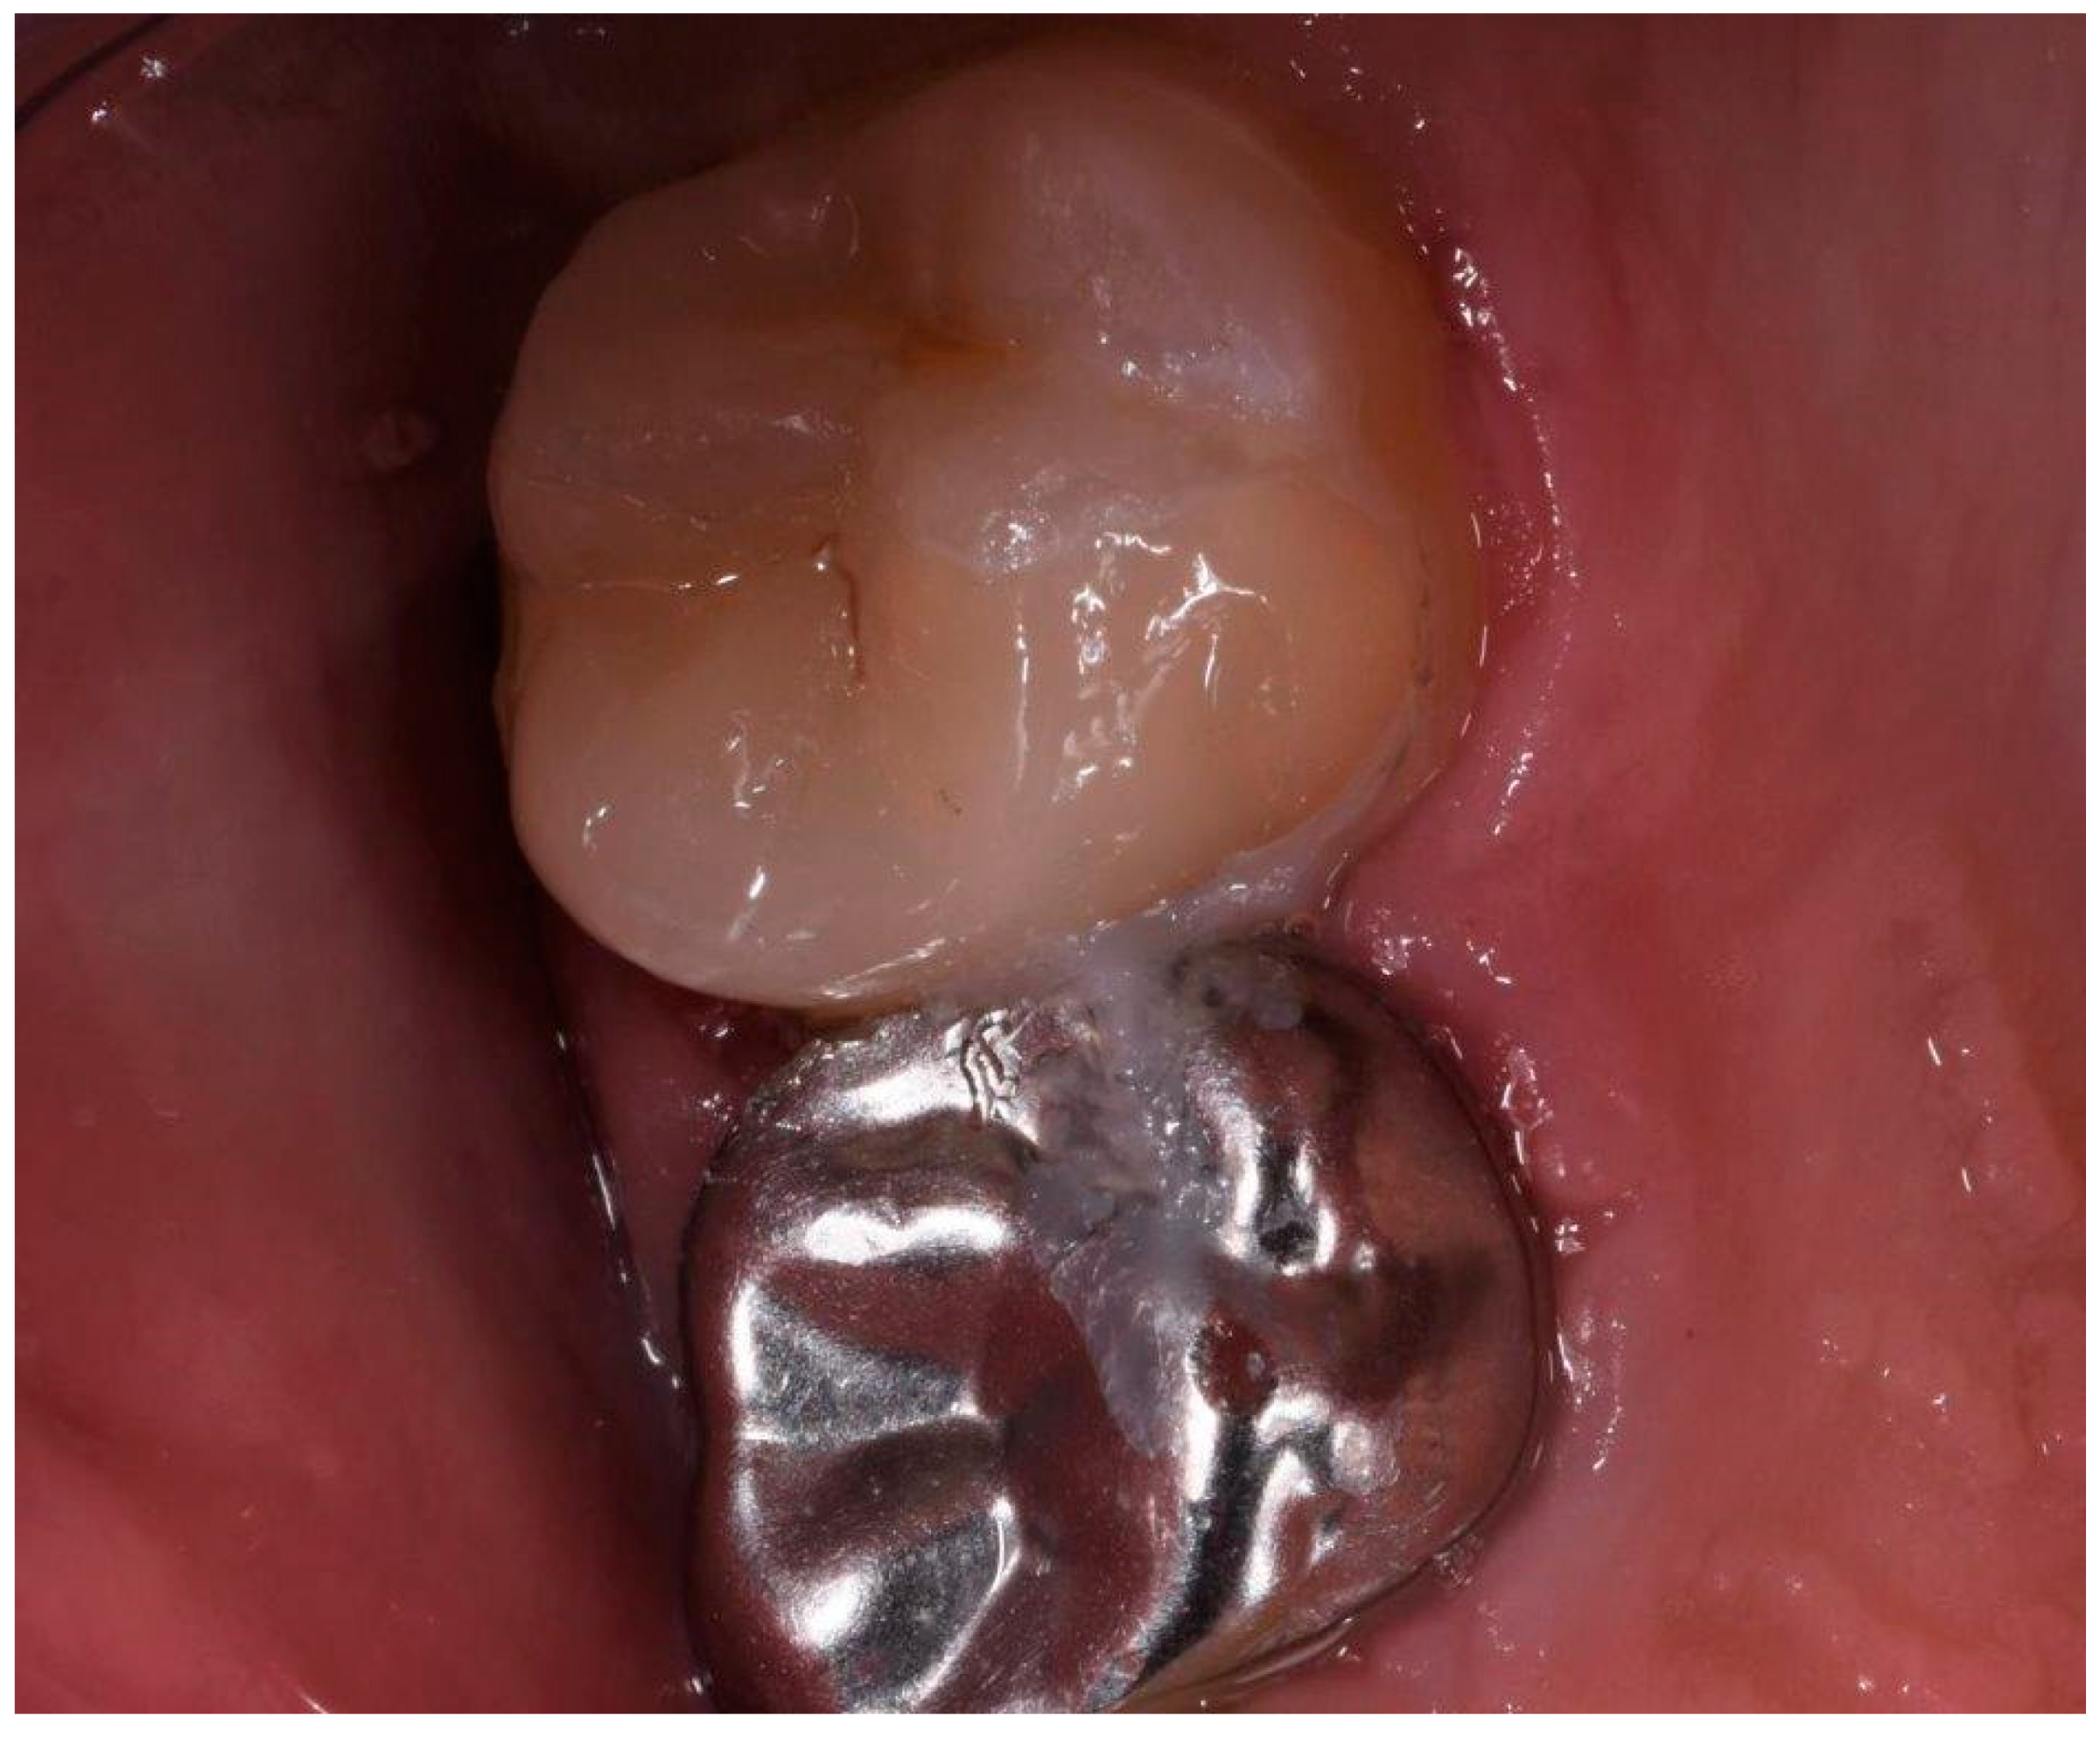

2.2. Clinical Case